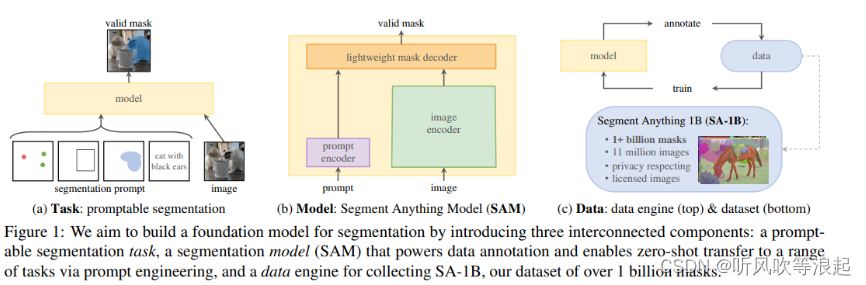

1、MedSAM 模型介绍

MedSAM全称为:Segment Anything in Medical Images

MedSAM 大模型利用了prompt engineering(提示工程)对指定区域进行分割

常见的分割提示有提示语、点、边界框等等,任务要求是收到提示符时至少输出一个有效的mask,哪怕提示是有歧义的

SAM通用分割大模型结构分为三个:图像编码器、提示器(prompt)和轻量级的解码器

这里的image encoder 输入size是1024*1024

关于SAM介绍可以自己百度或者阅读论文,这里只对代码简单介绍和复现